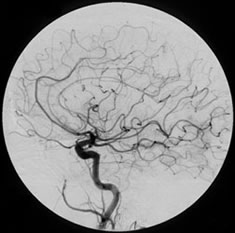

Carotid AngiogramA carotid or cerebral angiogram is a diagnostic test designed to show the condition of the blood vessels of the brain. X-ray contrast material is injected into an artery through a small tube (catheter), and X-ray images are obtained.

Carotid angiography is used to study the caliber of the carotid artery and look for stenosis that may be significant and cause an increased risk of stroke. Carotid angiography is performed with a routine angiographic procedure from the groin using thin catheters. Often both the carotid artery in the neck and the intracerebral vessels are studied at the same time.